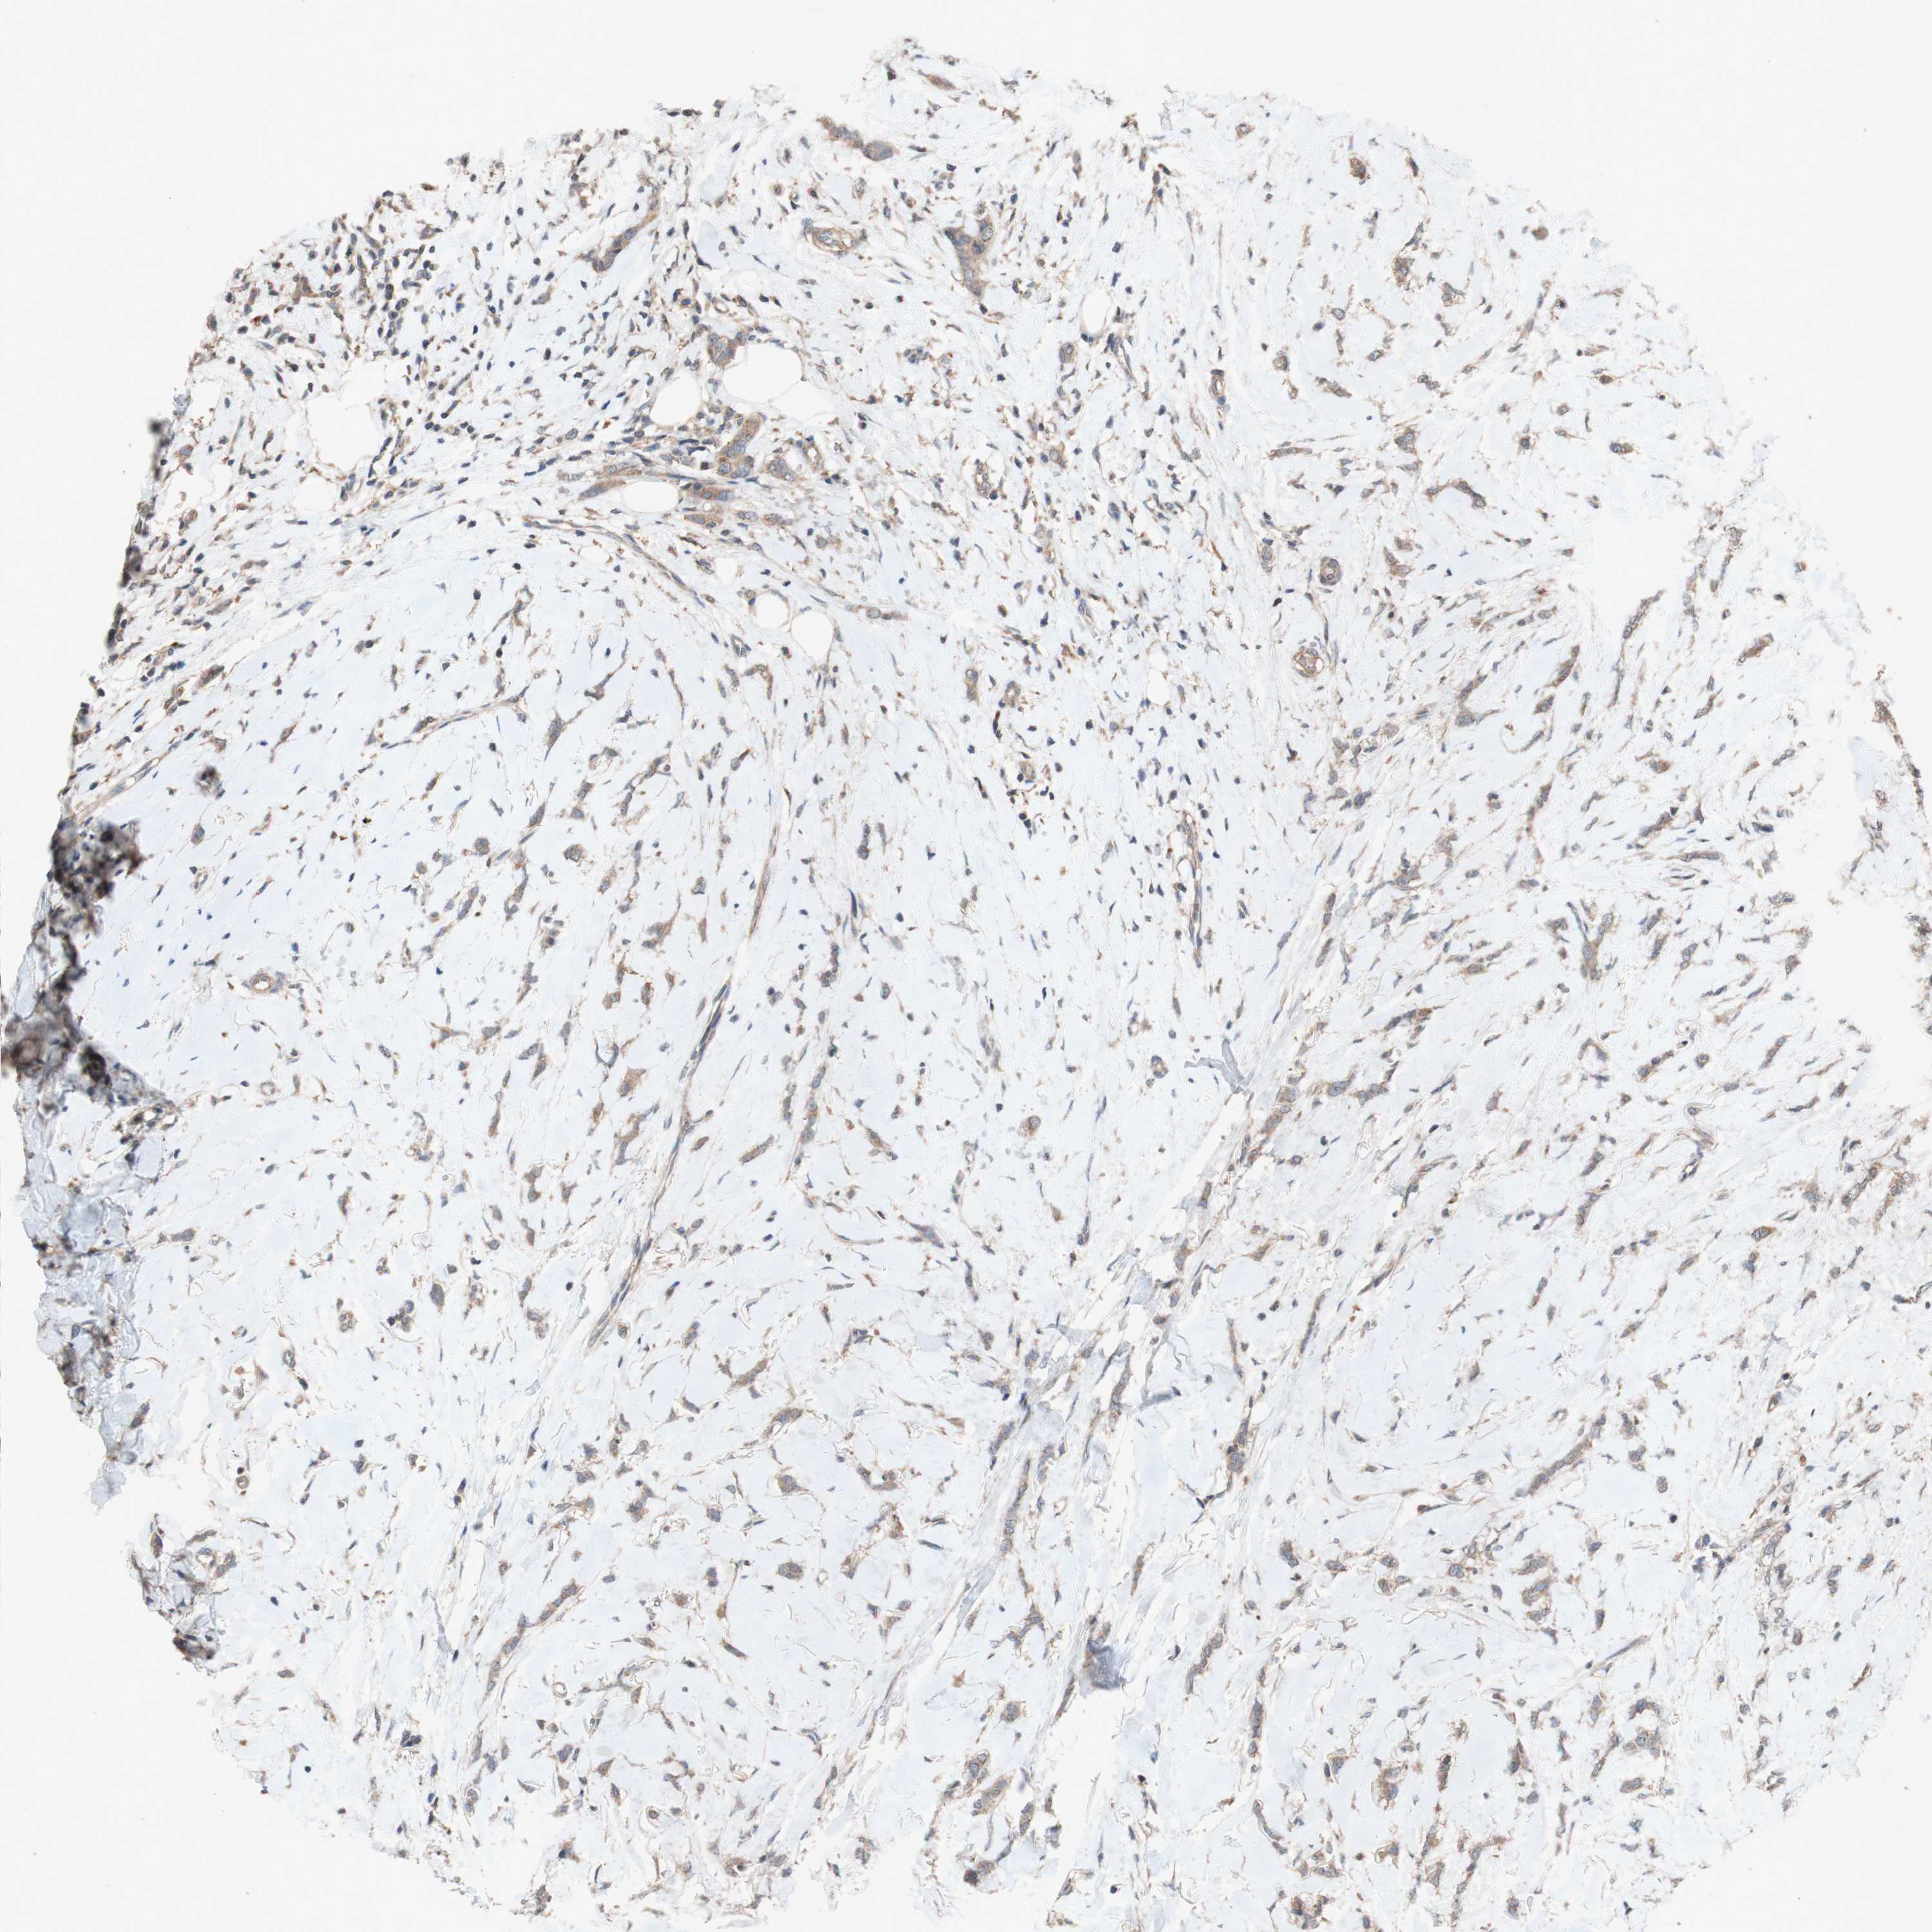

BRCA TCGA BRCA VALIDATION PROTEIN EXPRESSION